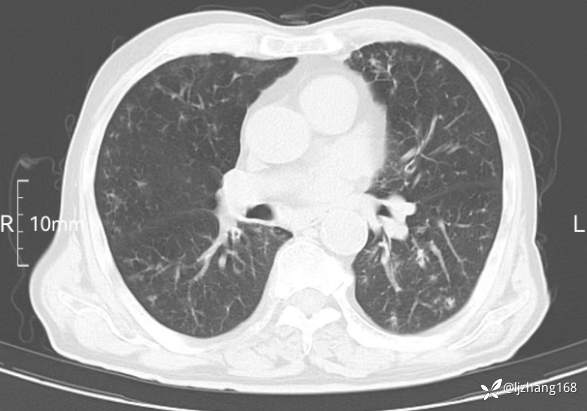

老年男患,咳嗽,气短,双肺多发间质性病变,何种感染?(有结果)

辅助检查:胸部CT:双肺肺气肿,间质性病变,血气分析:PH 7.413, PCO2 29.2mmHg, PO2,81.8mmHg,乳酸 3.3mmol/1,剩余碱-4.0mmol/1,HC03 18.8mmol/1。全血超敏C反应蛋白:超敏C反应蛋白 135.60 mg/L、 白细胞 14x19^9/L,中性粒细胞11.6x10^9/L。